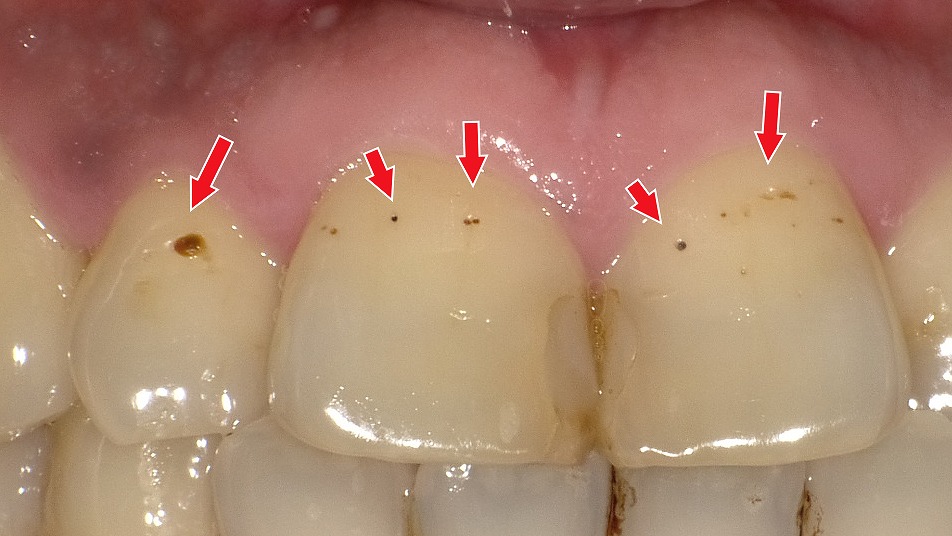

着色汚れ(ステイン)

初期虫歯(C0)

歯の溝や表面が黒く見える最も一般的な原因が初期虫歯です。エナメル質が溶け始めると、白濁や黒点として現れます。

特にC0(ごく初期の脱灰)の段階では、まだ穴が開いていないため削る治療は不要です。キシリトールガムやフッ素の活用、適切なブラッシングによって再石灰化を促すことで、虫歯の進行を止められる可能性が高く、予後観察で十分なケースが多いのが特徴です。

ただし、黒い点が目立って「見た目が気になる」という場合には、必要最小限に表面を整えたうえでコンポジットレジン充填(CR充填)で自然な色に修復する選択肢もあります。機能的な問題がない場合でも、審美的な改善を希望される方に適した治療です。